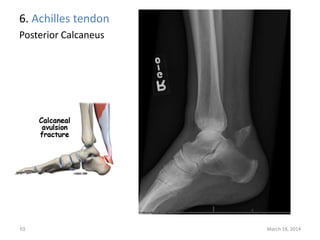

The document lists 10 common sites of avulsion fractures caused by the tearing away of tendons or ligaments from bone. It identifies the specific muscles or tendons that can cause avulsion fractures at the iliac crest, ischial tuberosity, greater trochanter, lesser trochanter, posterior calcaneus, olecranon process, superior patella, inferior patella, and tibial tuberosity.